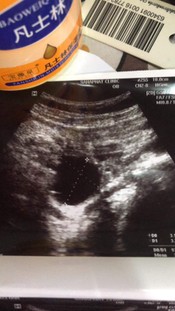

ตั้งครรภ์ 5 W 1 D

อัลตราซาวด์ทางช่องคลอดไม่พบถุงตั้งครรภ์ แบบนี้ยังมีโอกาสเจอไหมคะ หรือว่าน้องยังเล็กมากๆ